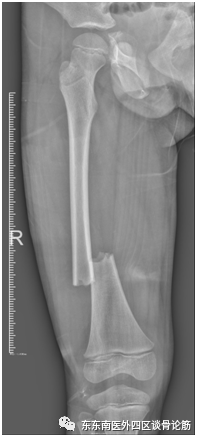

(术后X线)